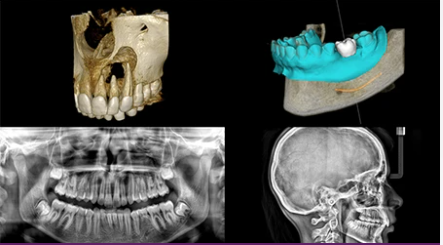

Une solution 4 en 1 qui combine la technologie panoramique, l’imagerie CBCT, la numérisation de modèles 3D et l’imagerie céphalométrique en option.

La résolution CBCT de 75 microns vous permet de visualiser les détails cliniques les plus infimes et est parfaitement adaptée aux indications endodontiques.

La technologie CS MAR*, avec une comparaison en direct unique, réduit automatiquement les artefacts métalliques. Cela vous aide à confirmer le diagnostic et réduit le risque d’erreur d’interprétation.

Avec son module optionnel Scan Ceph, le CS 8200 3D vous permet de réaliser des examens céphalométriques de haute qualité pratiquement en un instant. Numérisez les images en seulement 3 secondes* pour réduire le risque de flou de mouvement et obtenez des tracés entièrement automatisés en seulement 10 secondes.